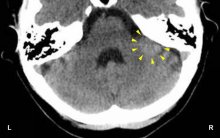

HEALING PHASE: During the healing phase the clouding of the vitreous body recedes. In PCL-A an edema (fluid accumulation) develops at the site, which increases the intraocular pressure in the eye. With the SYNDROME, that is, with water retention as a result of an active abandonment or existence conflict, the eye pressure rises even more. During the Epileptoid Crisis the edema is pressed out. However, in order to keep the eyeball firm and prevent it from collapsing, the intraocular pressure remains elevated during and shortly after the Epileptoid Crisis (in PCL-B). With a hanging healing due to continuous conflict relapses the optic nerve becomes damaged, particularly when the edema reaches into the opening of the vitreous where the optic nerve leaves the eye. In conventional medicine, damage to the optic nerve is called a glaucoma or “green cataract” (compare with “grey cataract” related to the lens).